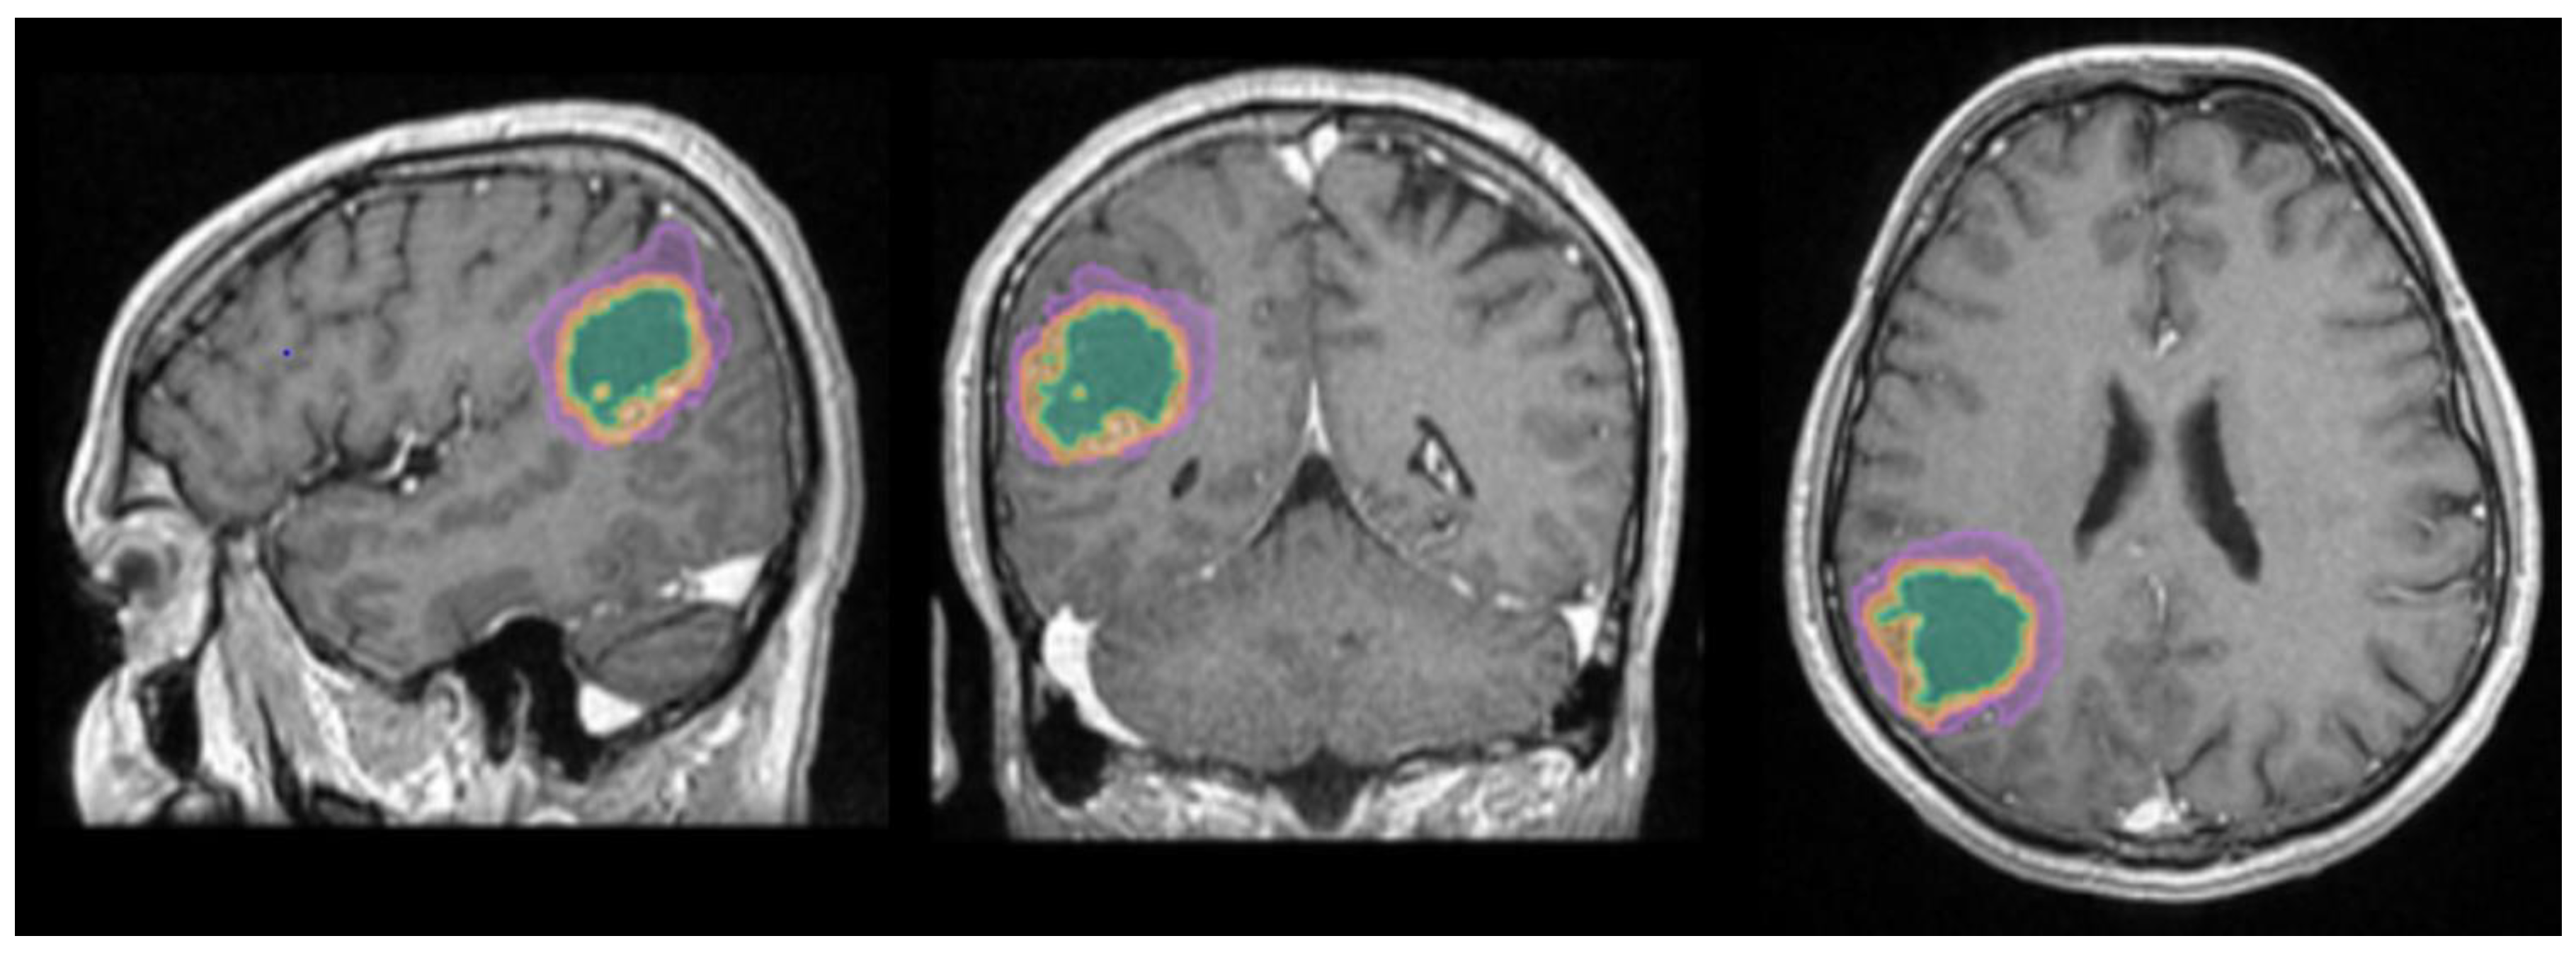

Figure 1.

Mdbrain processing of MRI brain acquisition (DICOM). T1W CE in sagittal, coronal and respectively axial planes. View of the three regions that were calculated separately for every patient: green – necrosis, orange – enhancing part of the tumor and purple – perilesional edema (approval was obtained from the Ethics Committee of the University of Medicine and Pharmacy “Grigore T. Popa” Iasi). .